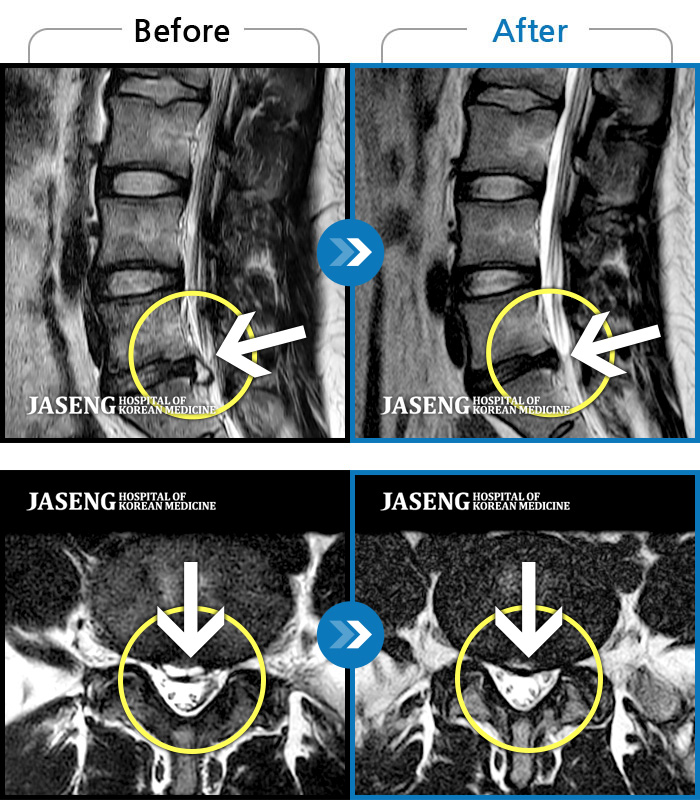

MRI로 보는 치료결과

1,169건의 MRI 전후 사진으로

터진 디스크 흡수 사례를 확인하세요.

[촬영시기:22.05.27~24.11.02]

[촬영시기:22.05.27~24.11.02]

[천안_허리디스크] 직업 상 무거운 물건을 많이 드는 편으로 6개월간 허리와 둔부의 통증이 지..조회수 3 2024.11.21